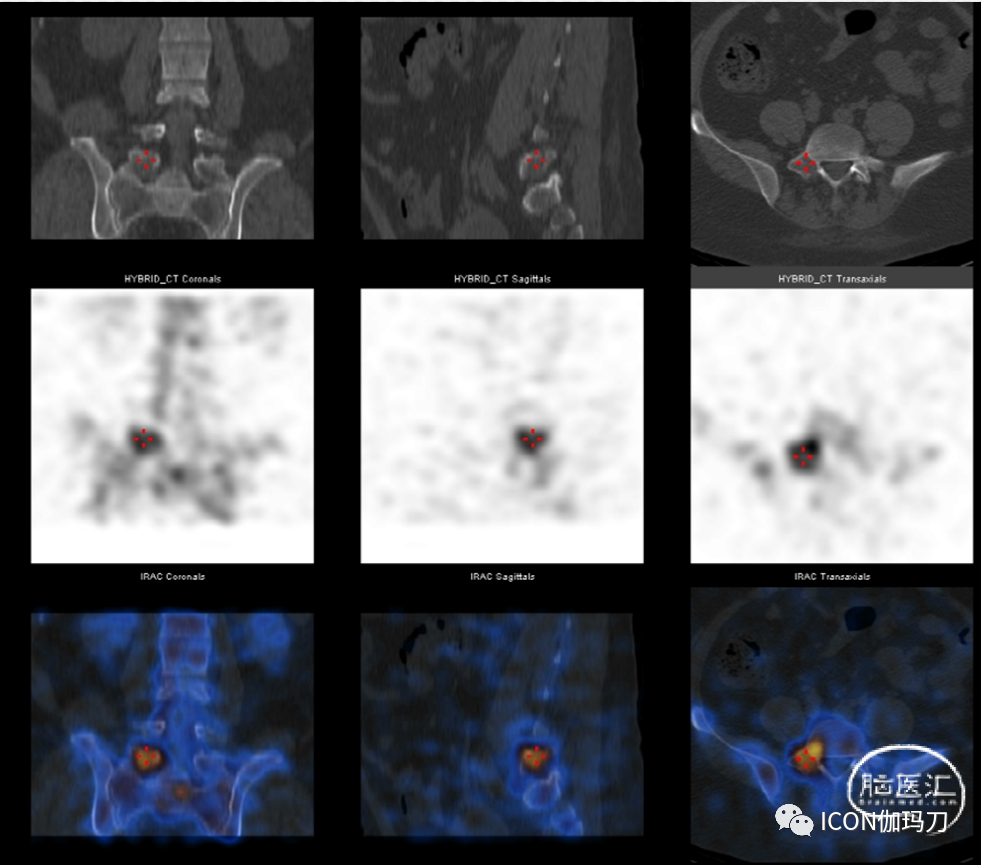

她经历了左眼视力丧失,MRI报告肿瘤体积显著增加,并压迫视交叉(图3E和F),血清泌乳素水平升至200.0 ng/ mL(未稀释样本)(补充图1)。行第四次经颅垂体瘤次全切除术(图3G和H);然而,视力下降没有改善,术后出现中枢系统感染。经抗生素治疗及腰椎引流后,中枢系统感染治愈。垂体肿瘤切除后的病理结果显示Ki-67指数增加到20%(图4F)。2016年3月,她面对痛苦和软弱的右腿,和MRI显示硬膜内的类似质量的第四腰椎(图3 I和J)。全身ECT等报道,多个高代谢(hypermetabolic)焦点被发现在第五腰椎(补充图2),血清泌乳素水平再次升至200.0 ng/mL(标本未稀释)(补充图1)。经后路硬膜外病变完全切除(图3K和L)。术后右腿疼痛和无力明显恢复。但血清泌乳素水平没有显著下降(补充图1)。切除的椎管内肿瘤的组织学检查显示,免疫组化(IHC)PRL为强阳性,而其他垂体激素为阴性。Ki-67指数上升到30%(图4H和I)。病理结果与分泌泌乳素垂体癌(PCs)的转移一致。随访期间,血清泌乳素水平持续升高,2016年10月最后一次血清泌乳素检测结果为356.0 ng/mL(补充图1)。不幸的是,鞍区肿瘤继续快速进展,患者于2017年10月死亡。

补充图2